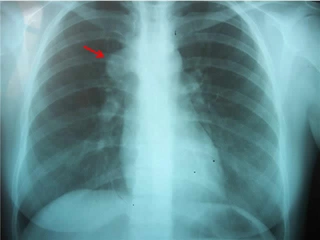

Temiz Akciğer Tomografisi Ne Anlama Geliyor?Günümüzde tıpta tanı ve tedavi süreçlerinde önemli bir yer tutan görüntüleme yöntemlerinden biri olan akciğer tomografisi, hastalıkların teşhisinde kritik bir rol oynamaktadır. "Temiz akciğer tomografisi" ifadesi, genellikle akciğerlerde herhangi bir anormal bulguya rastlanmadığı anlamına gelir. Bu bağlamda, temiz bir akciğer tomografisi sonucu, hastanın akciğer sağlığının iyi olduğunu gösterir. Akciğer Tomografisi Nedir?Akciğer tomografisi, yüksek çözünürlüklü görüntüler elde etmek için X-ray teknolojisini kullanan bir görüntüleme yöntemidir. Bu yöntem, akciğerlerin iç yapısının detaylı bir şekilde incelenmesine olanak tanır. Tomografi, akciğerlerdeki lezyonlar, tümörler, enfeksiyonlar ve diğer patolojilerin tespit edilmesinde son derece etkili bir yöntemdir. Temiz Akciğer Tomografisi SonucuTemiz bir akciğer tomografisi sonucu, şu durumları ifade edebilir: